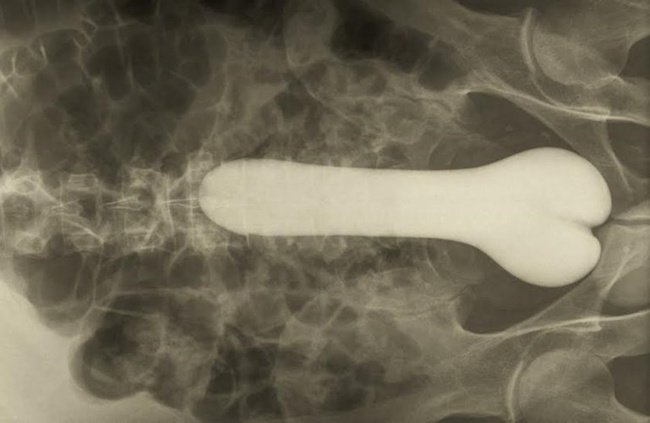

Dương vật giả

Một người đàn ông phải tìm đến bệnh viện cầu cứu bác sĩ do đau ở trực tràng vì đã nhét chiếc dương vật giả vào hậu môn nhưng không thể gắp nó ra.